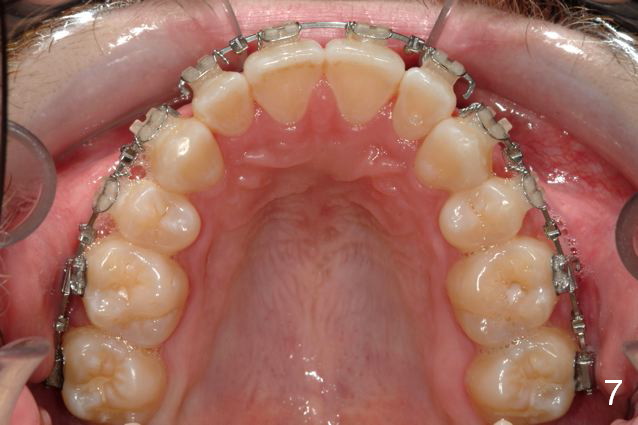

Initial bonding on 08/04/2014 (Fig.1-3); follow up appointments (09/20/2014 (Fig.4,5); 11/11/2014 (Fig.6,7), prepared for maxillary segmental surgery to expand, advance, and level.

I routinely start off with a round NiTi AW, like .014 in the .018 slot, then to .016 and up to 16X22 NiTi. Then I go to rectangular SS.  I segmented the AW to facilitate the surgery.

Mine are crimpable. Very convenient, you just squeeze them onto the AW right where u want them. I provide them for the oral surgeon for jaw surgery cases.